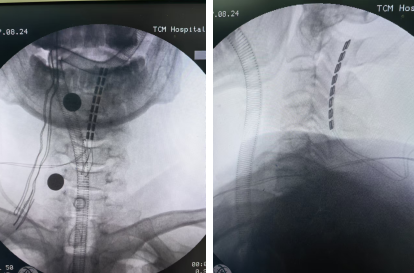

8月17日,范家权主任带领团队为患者实施手术,将脊髓神经刺激电极置于高位颈髓(C2-C4)硬膜外腔隙,手术顺利,患者安返病房。

image.png

8月26日,医生通过外部程控仪对患者进行了开机测试,采用全新的BURST刺激模式,开机后,参数反馈一切正常;次日患者肌张力即较前略有降低,睁眼时间较前延长。